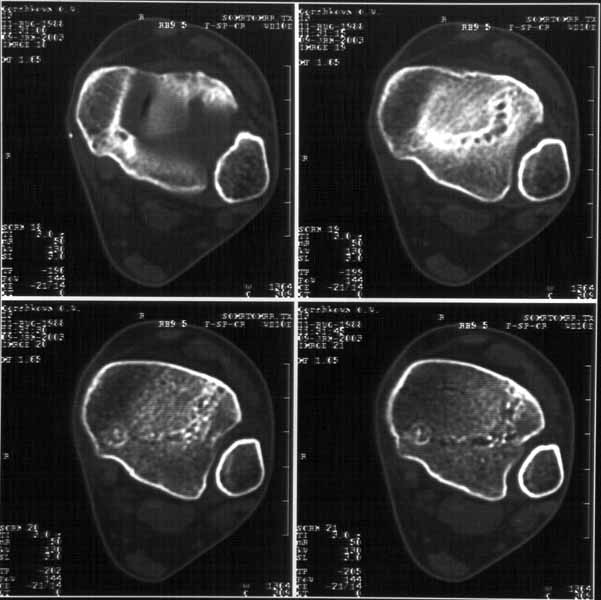

На следующий день пациентке сделали КТ. Может быть, после просмотра картинки будут другие предложения? Не убрать ли ве-таки этот фрагмент

позади внутренней лодыжки, который оттесняет таран кнаружи?

Здесь 4 среза, начиная от основания лодыжки и проксимальнее. Где, по Вашему мнению, проходит линия перелома, отделяющая переднюю часть внутренней лодыжки от большеберцовой кости? Заранее спасибо.

38KB (39385 bytes)